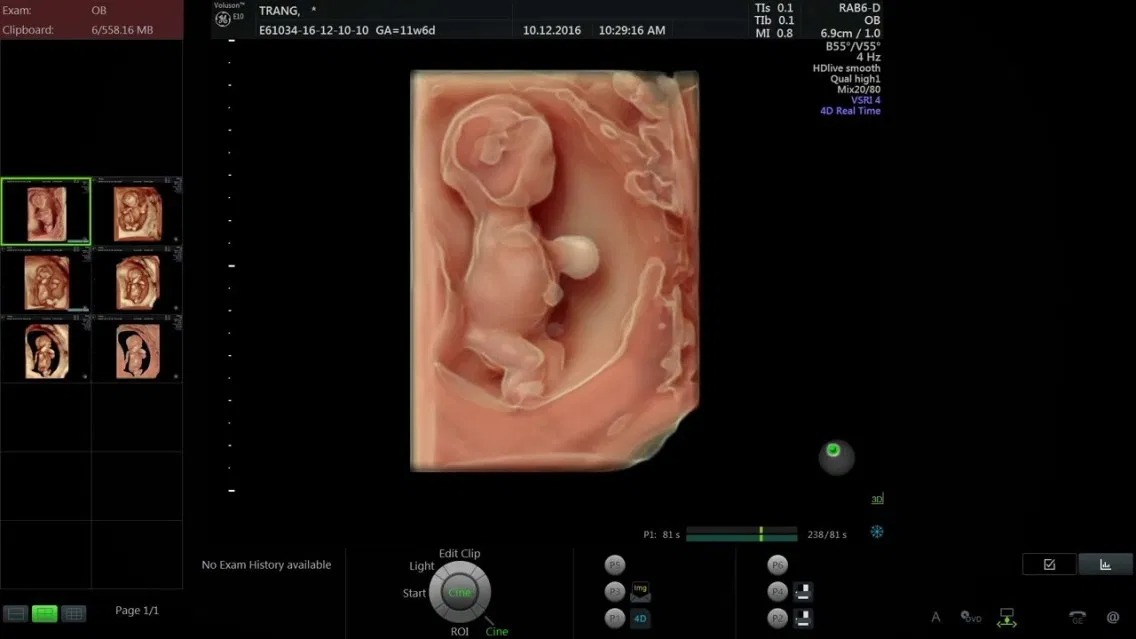

Khá nhiều mẹ bầu thắc mắc liệu thai 11 tuần đã biết trai hay gái chưa. Thực tế, giới tính của thai nhi có thể xác định được thông qua bộ phận sinh dục chớm xuất hiện ở tuần thai thứ 11. Tuy vậy, nếu mẹ bầu muốn kiểm tra giới tính bé vào lúc này, vẫn rất khó để có thể xác định chính xác. Nguyên nhân là do kích thước thai nhi còn quá nhỏ nên khó nhìn rõ bộ phận sinh dục thai nhi 11 tuần. Một số cơ quan nội tạng quan trọng đã hoàn thiện chức năng và bắt đầu đi vào hoạt động. Hồng cầu bắt đầu hình thành trong gan của bé.

Thai nhi 11 tuần tuổi vẫn đang hình thành bộ phận sinh dục. Với bé trai, từ tuần thứ 10 trước đó, chồi sinh dục đã trở thành tuyến tiền liệt. Với bé gái, ở tuần thứ 11, bé xuất hiệu buồng trứng. Thông qua hình ảnh siêu âm, bác sĩ có thể nhìn thấy được hình dáng bên ngoài của thai nhi và đoán được giới tính của con. Tuy nhiên, việc xác định giới tính ở thời điểm này có độ chính xác không cao bởi thai nhi vẫn còn quá nhỏ, hình ảnh thai 11 tuần tuổi ghi nhận được không nhìn rõ bộ phận sinh dục. Hơn nữa, việc xác định giới tính thai nhi 11 tuần còn phụ thuộc vào tư thế nằm của bé, chất lượng máy siêu âm, trình độ của bác sĩ…

Thai nhi 11 tuần tuổi đã phát triển đầy đủ các ngũ quan trên khuôn mặt cũng như hình dáng tay, chân bên ngoài và các cơ quan thuộc hệ tiêu hóa, hệ bài tiết, hệ thần kinh... Đây là khoảng thời gian thích hợp cho mẹ bầu tiến hành siêu âm nhằm kiểm tra sức khỏe thai nhi toàn diện. Phương pháp này sẽ tiến hành đo độ mờ da gáy của thai nhi rồi dựa vào những số liệu thu thập được để phát hiện ra thai nhi có bị dị tật bẩm sinh hay không.

Nếu kết quả thu được cho biết chỉ số mờ da gáy của thai nhi 11 tuần là 2mm, điều đó có nghĩa thai nhi khỏe mạnh bình thường và không bị dị tật. Tuy nhiên, nếu con số này tăng lên hoặc giảm đi, em bé khi sinh ra có nguy cơ bị dị tật cao với một số bệnh thường gặp như bệnh down, hở hàm ếch... Mẹ bầu cần lưu ý tiến hành siêu âm đúng thời điểm, thường là từ tuần thứ 11 đến tuần thứ 14 để phát hiện dị tật sớm nhất và có hướng điều trị hiệu quả.